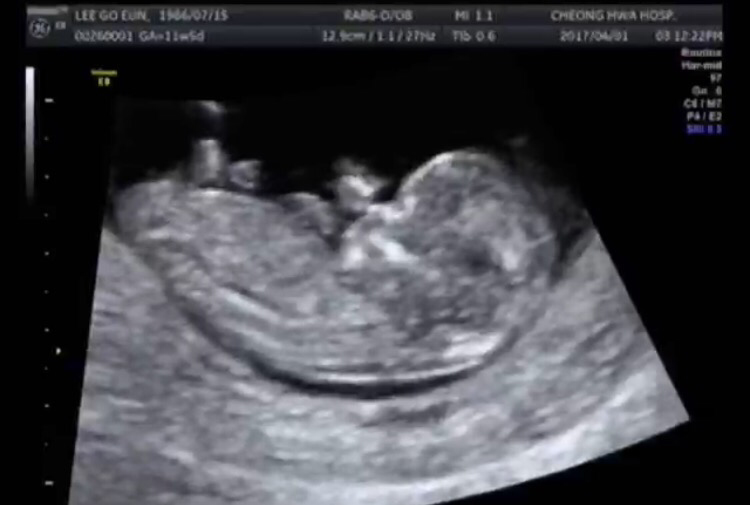

11주차, 손발이 또렷한 Jambo. 지금은 얼마나 더 컸으려나-